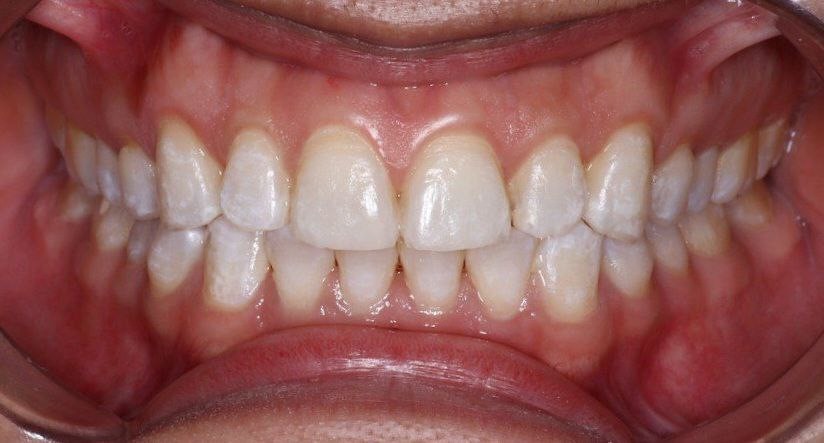

Siete días después, una nueva evaluación clínica y fotográfica fue realizada observando evidente mejora en el aspecto estético del esmalte; disminución de las manchas blanco opacas y un aumento notable en la autoestima del paciente (figura 5). El paciente recibió instrucciones de acudir a controles a los 3 y 6 meses posteriores al tratamiento, observando mantenimiento de los resultados obtenidos.

Figura 5. Control a los 7 días